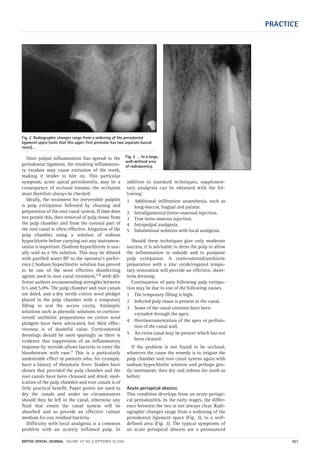

Acute periapical abscess

This condition develops from an acute periapi-

cal periodontitis. In the early stages, the differ-

ence between the two is not always clear. Radi-

ographic changes range from a widening of the

periodontal ligament space (Fig. 2), to a well-

defined area (Fig. 3). The typical symptoms of

an acute periapical abscess are a pronounced

Fig. 2 Radiographic changes range from a widening of the periodontal

ligament space (note that this upper first premolar has two separate buccal

roots)…

Fig. 3 … to a large,

well-defined area

of radiolucency.

06p299-305.qxd 24/08/2004 11:26 Page 301

soft-tissue swelling (Fig. 4) and an exquisitely

tender tooth. Extrusion from the socket will

often cause the tooth to be mobile. Differential

diagnosis of a suspected periapical swelling is

important in case the cause is a lateral peri-

odontal abscess. The diagnosis can be made by

testing the vitality of the tooth. If it is vital, then

the cause may well be periodontal in origin.